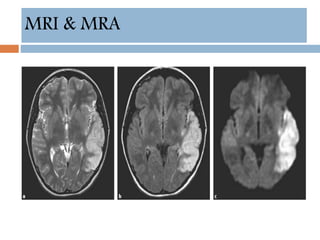

MRI & MRA